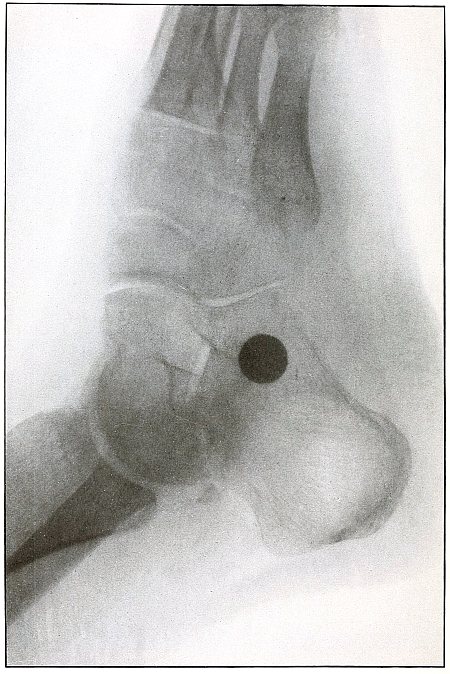

| 73. |

Gunshot wound, heel |

156 |

| 74. |

Gunshot wound, heel |

158 |